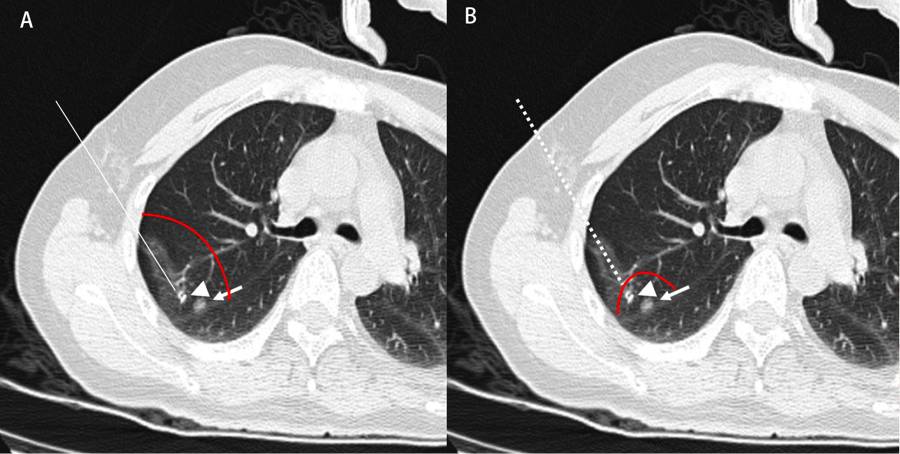

如下图所示,术前CT发现右上叶混合GGO,靠近叶间裂,同时有肩胛骨遮盖,影像提示早期肺癌,拟行手术切除。Hookwire或传统Microcoil定位由于解剖位置限制,会造成针道过长,导致不必要的正常肺组织损失。陈昶教授提出的改良方法选择外侧胸壁进针,于结节附近释放弹簧圈,就结节行小部分楔形切除,最终病理报告微浸润腺癌(图4)。此方法简单可行,推广价值高,相对于Hookwire或传统Microcoil定位而言可极大地保留盲区结节患者的肺组织,在术后恢复方面有着极为重要的意义。陈昶教授团队将此方法经验总结并发表于SCI期刊2,获得国内外专家一致认可。

图4 盲区定位实例图

A,Hookwire或传统Microcol定位切除范围;B,改良法切除范围。

实线及虚线:金属针定位针道;三角形:弹簧圈;箭头:病灶;红曲线:切除范围。